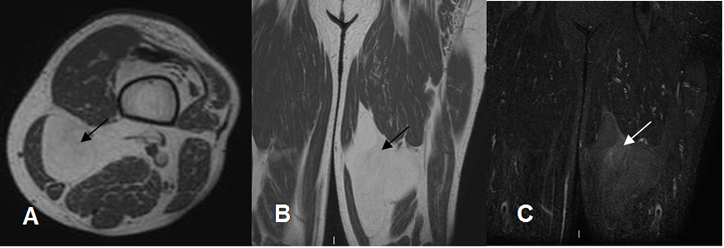

Fig 161. Lipoma.

A: RM axial en T1, B: RM axial en T2 y C: RM axial en STIR. Lesión ovalada y encapsulada en la parte interna del pie, hiperintensa en T1 y T2 y que suprime en STIR, que corresponde a lipoma.

Fig 163 A. Lipoma.

A: Rx AP y B: RM coronal en T1 y C: RM coronal en STIR. Gran prominencia en los tejidos blandos de la parte lateral de la rodilla, por tejido graso que corresponde a lipoma no encapsulado.